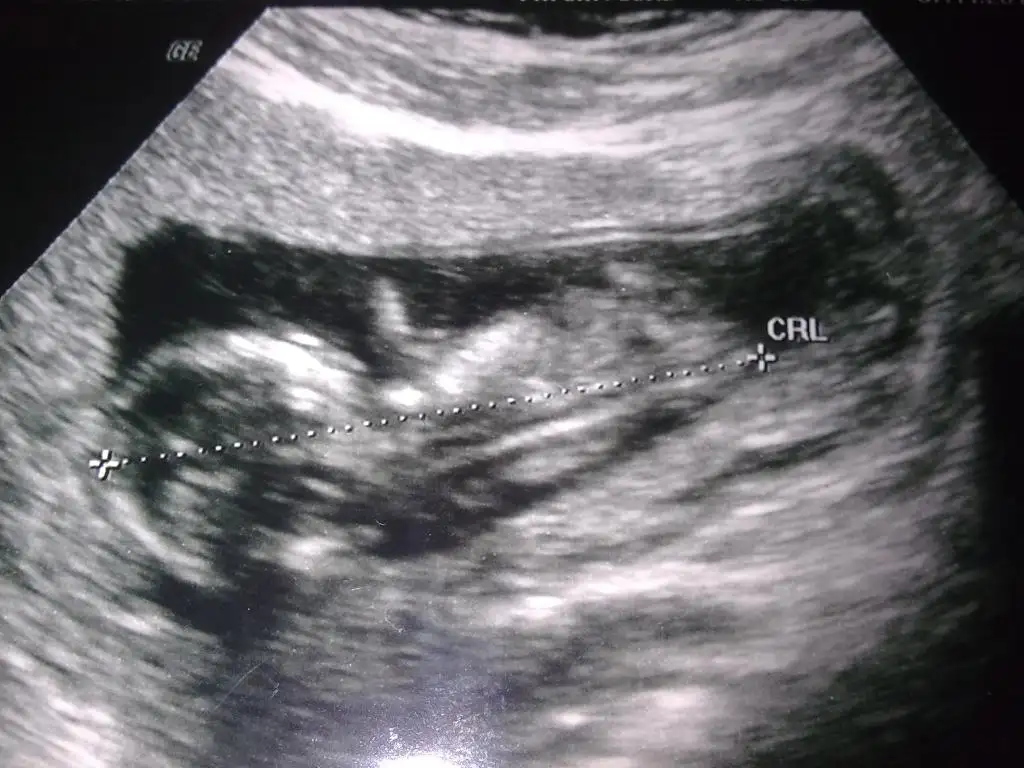

dr soylemeden siz gorun genital nub teorisi ( bebegin cinsiyeti)

Merhaba biz de 12+ 4 üz acaba benim bebeğimin cinsiyetini tahmin edebilirmisiniz resim çok net değil.

görüntüler 11+0 yani 12. haftanın içine girmiş bulunuyoruz.